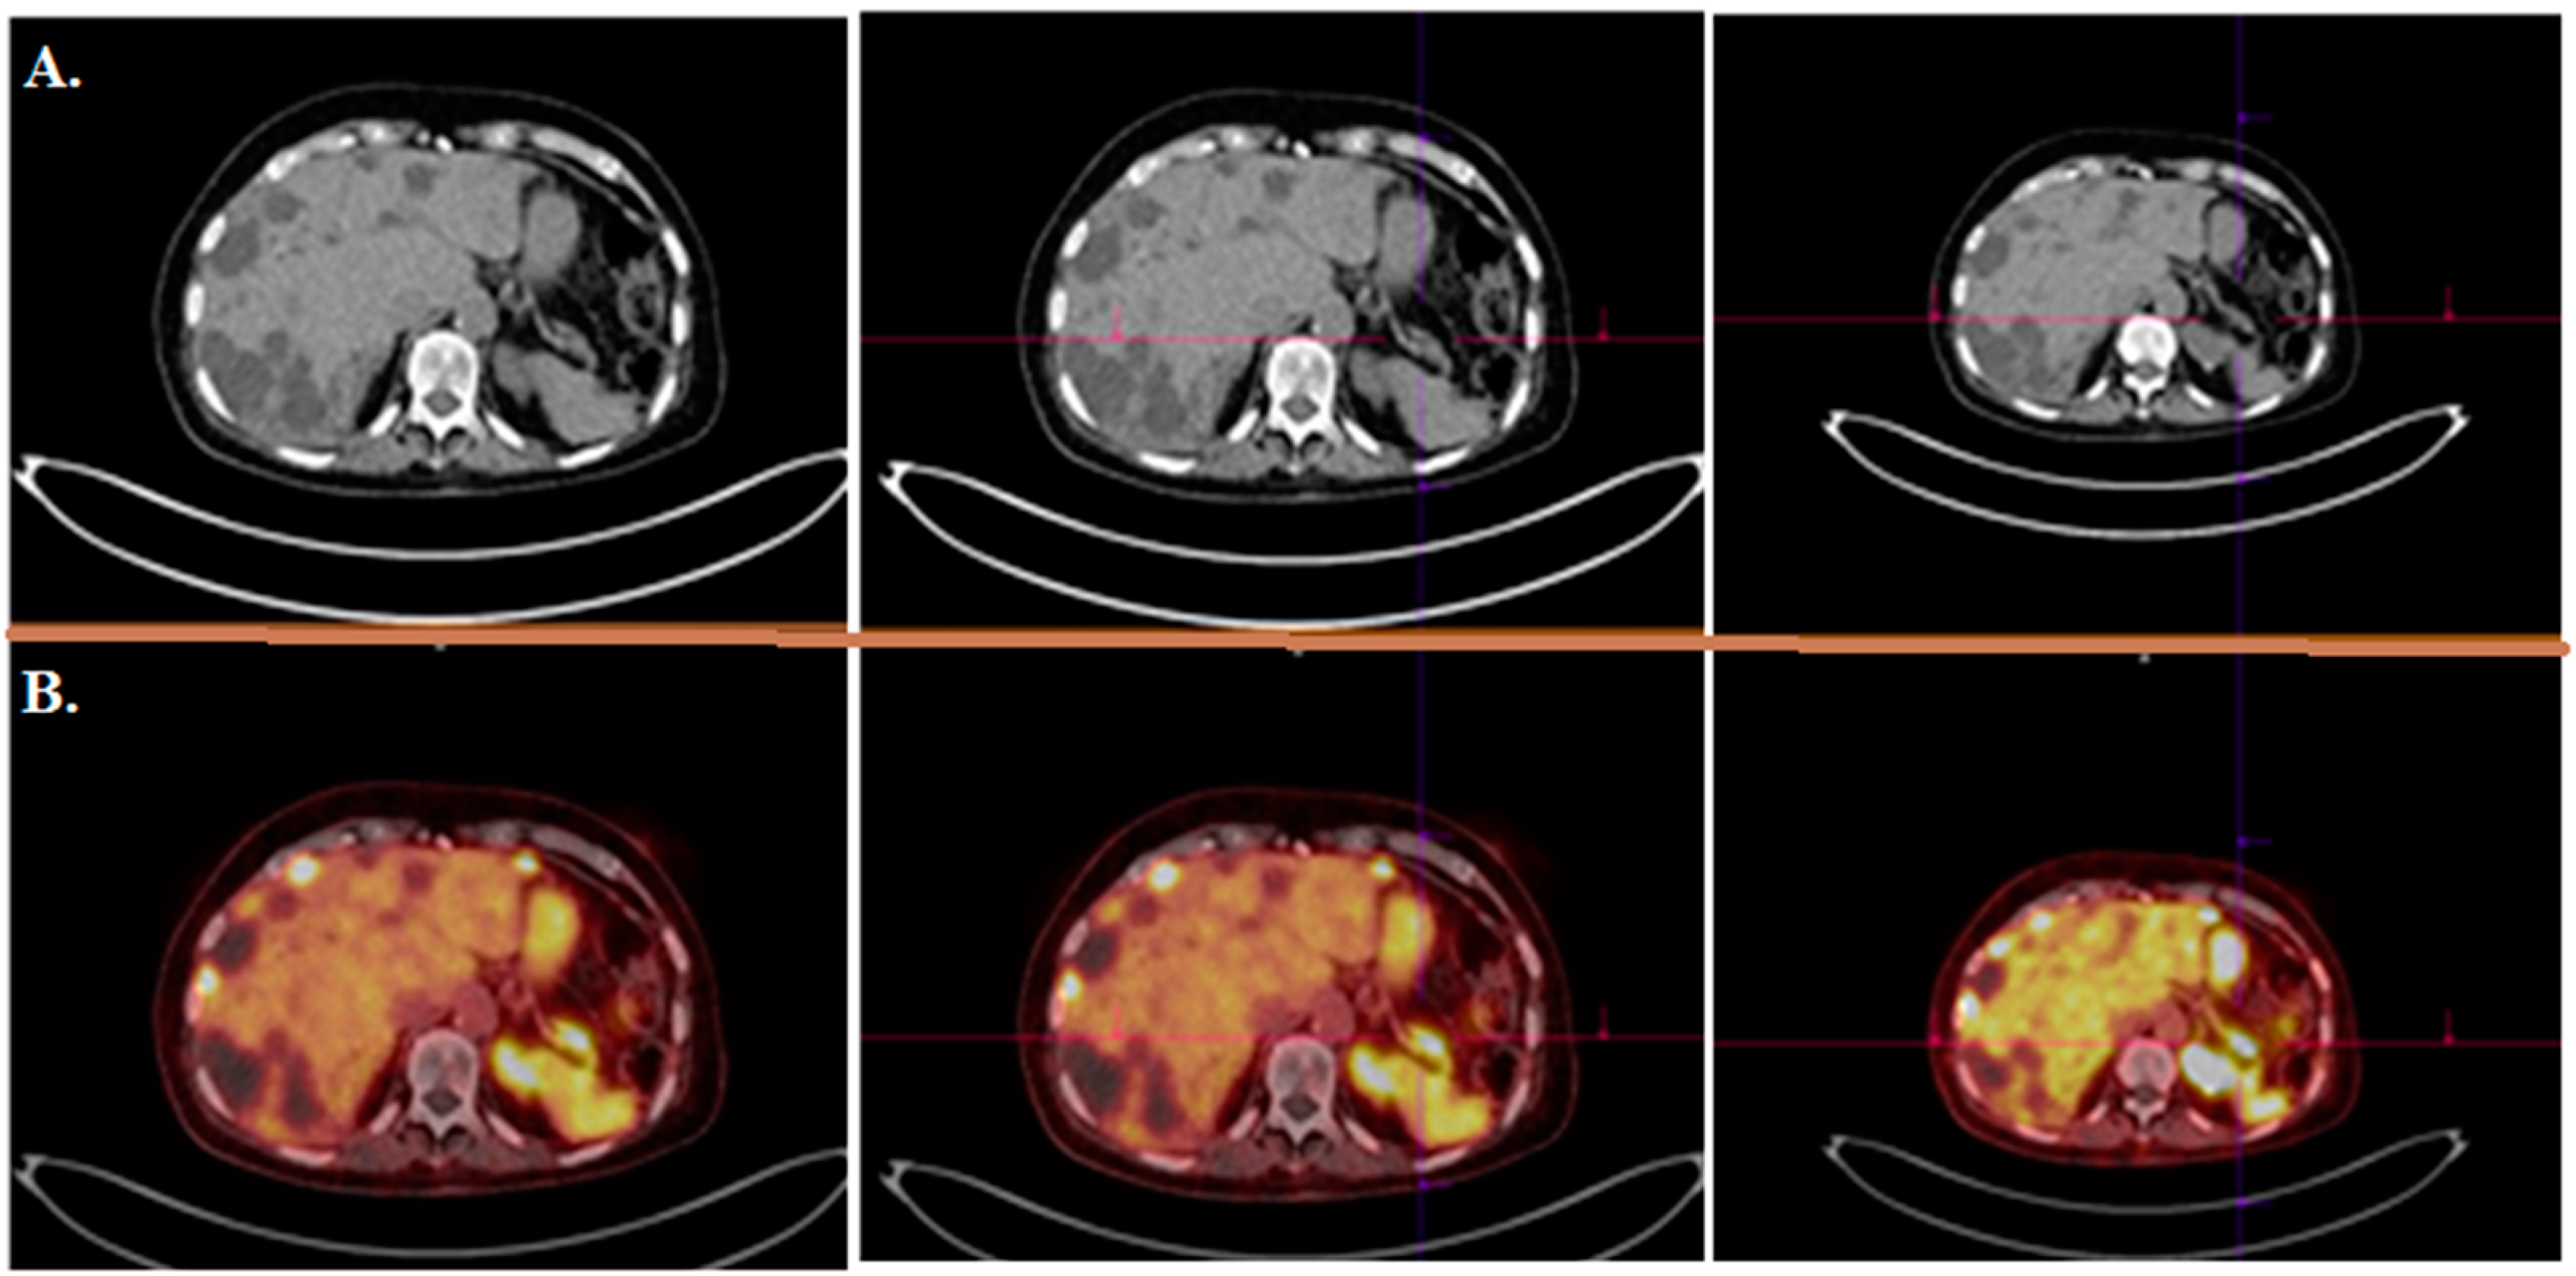

- Mirzaei, S.; Revheim, M.-E.; Raynor, W.; Zehetner, W.; Knoll, P.; Zandieh, S.; Alavi, A. 64Cu-DOTATOC PET-CT in patients with neuroendocrine tumors. Oncol. Ther. 2020, 8, 125–131. [Google Scholar] [CrossRef]

- Pfeifer, A.; Knigge, U.; Mortensen, J.; Oturai, P.; Berthelsen, A.K.; Loft, A.; Binderup, T.; Rasmussen, P.; Elema, D.; Klausen, T.L. Clinical PET of neuroendocrine tumors using 64Cu-DOTATATE: First-in-humans study. J. Nucl. Med. 2012, 53, 1207–1215. [Google Scholar] [CrossRef]

- Delpassand, E.S.; Ranganathan, D.; Wagh, N.; Shafie, A.; Gaber, A.; Abbasi, A.; Kjaer, A.; Tworowska, I.; Núñez, R. 64Cu-DOTATATE PET/CT for imaging patients with known or suspected somatostatin receptor–positive neuroendocrine tumors: Results of the first US prospective, reader-masked clinical trial. J. Nucl. Med. 2020, 61, 890–896. [Google Scholar] [CrossRef]

- Loft, M.; Carlsen, E.A.; Johnbeck, C.B.; Johannesen, H.H.; Binderup, T.; Pfeifer, A.; Mortensen, J.; Oturai, P.; Loft, A.; Berthelsen, A.K. 64Cu-DOTATATE PET in patients with neuroendocrine neoplasms: Prospective, head-to-head comparison of imaging at 1 hour and 3 hours after injection. J. Nucl. Med. 2021, 62, 73–80. [Google Scholar] [CrossRef] [PubMed]

| [64Cu]Cu-DOTA-TOC | NET | 33 | 2019 | High detection rate and high target to background ratio in images raised [64Cu]Cu- DOTA-TATE as a promising and safe radiolabeled SST derivative for NET detection | [22] |